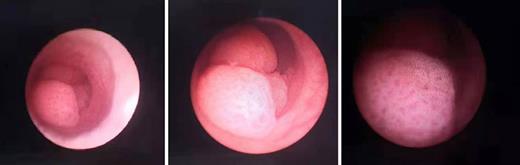

Three months later, urethrocystoscopy was performed for postoperative check, and a cauliflower-like neoplasm was found 1 cm away from the left ureteral orifice in the bladder (shown in Fig. 2). The renal pelvis was also checked, but there was no neoplasm in it. Biopsy was taken from the neoplasm in the bladder, and later pathological finding showed that it was urothelial carcinoma in situ. Five days later, transurethral resection of bladder tumor (TURBT) was conducted.